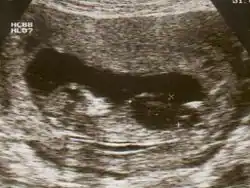

Ultrasound of fetus with Down syndrome showing a large bladder | |

Fetal megacystis[1] is a rare disease that is identified by an abnormally large or distended bladder.

Fetal megacystis is diagnosed during pregnancy by ultrasound imaging procedures. Since it can be associated with genetic abnormalities, further ultrasounds and tests may be administered during pregnancy. It may also be diagnosed as megalocystis, and/or termed megabladder, which is the same condition.